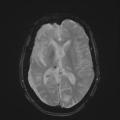

Encéphalite de Rasmussen

ENCEPHALITE

Image